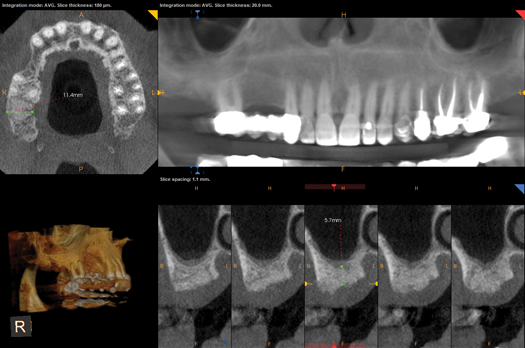

Fig 5. CBCT revealed residual bone height less than 6 mm.

Figure 5

Upon evaluation of the CBCT using a metal artifact reduction (MAR) tool it was determined that either a short implant be placed or an internal sinus elevation procedure be performed to allow placement of a more robust implant. The CBCT showed less than 6 mm of residual bone height (Figure 5) available before the Schneiderian membrane of the maxillary sinus would be breached. After a review of available options, the patient elected to have the sinus elevation done and a longer implant placed with the use of guided surgery. Due to the limited access in the posterior of the oral cavity, the use of a static surgical guide might have proved difficult because of spatial and visual constrictions. Therefore, dynamic virtual navigation was chosen for this procedure.

Fig 10. CBCT revealed relatively non-complex implant placement on

the maxillary right side for the maintenance of 3 mm between each

implant and less than 6 mm residual bone height on the maxillary left

side.

Figure 10